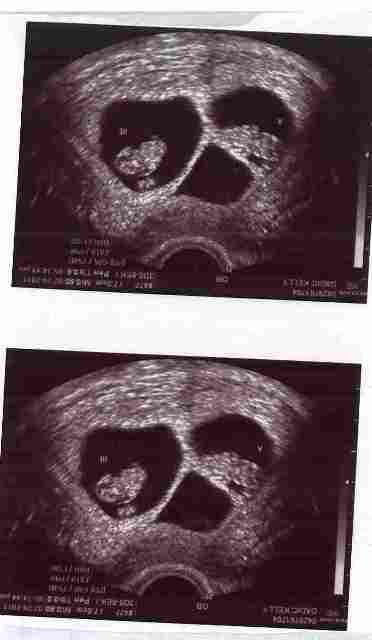

So here is my little "thing 1" and "thing 2" at 8w2d (yesterday).

(We originally were blessed with triplets, but sadly Baby B did not develop you can see the third sac in the pics)